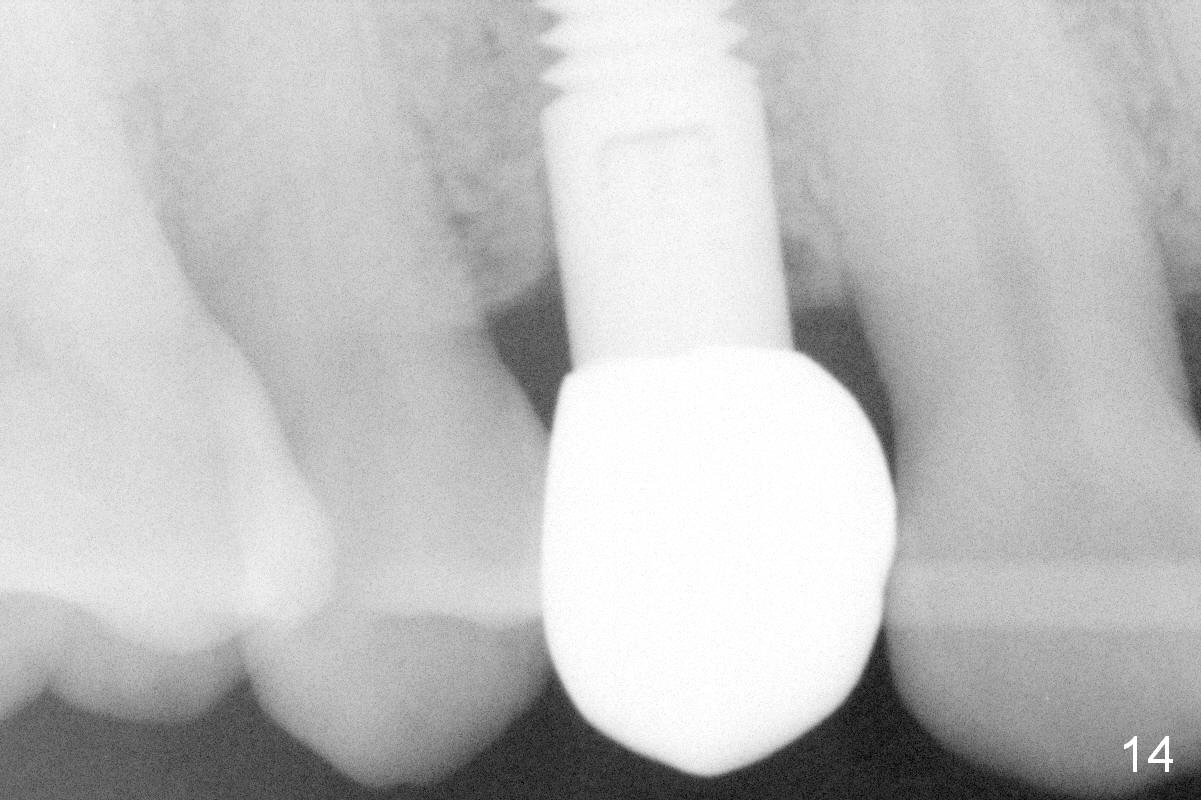

The patient returns 6 months postop for impression of a permanent restoration. The gingiva with knife-edged papillae adapts to the provisional (Fig.7). The gingiva looks healthy when the provisional is removed (Fig.8). The buccal bone resorption seems to be minimal, as compared to Fig.1,2. There is no bone loss between immediately postop (Fig.9 I; implant), 4.5 months postop (Fig.10 A: abutment), 4 and 7 months post cementation (Fig.11,12 C: crown). Soft and hard tissue morphology remains normal 7 months post cementation (Fig.13). No bone loss is observed 15 months post cementation (Fig.14). The papillae (Fig.15) and bone (Fig.16,17) remain stable 29 months post cementation.